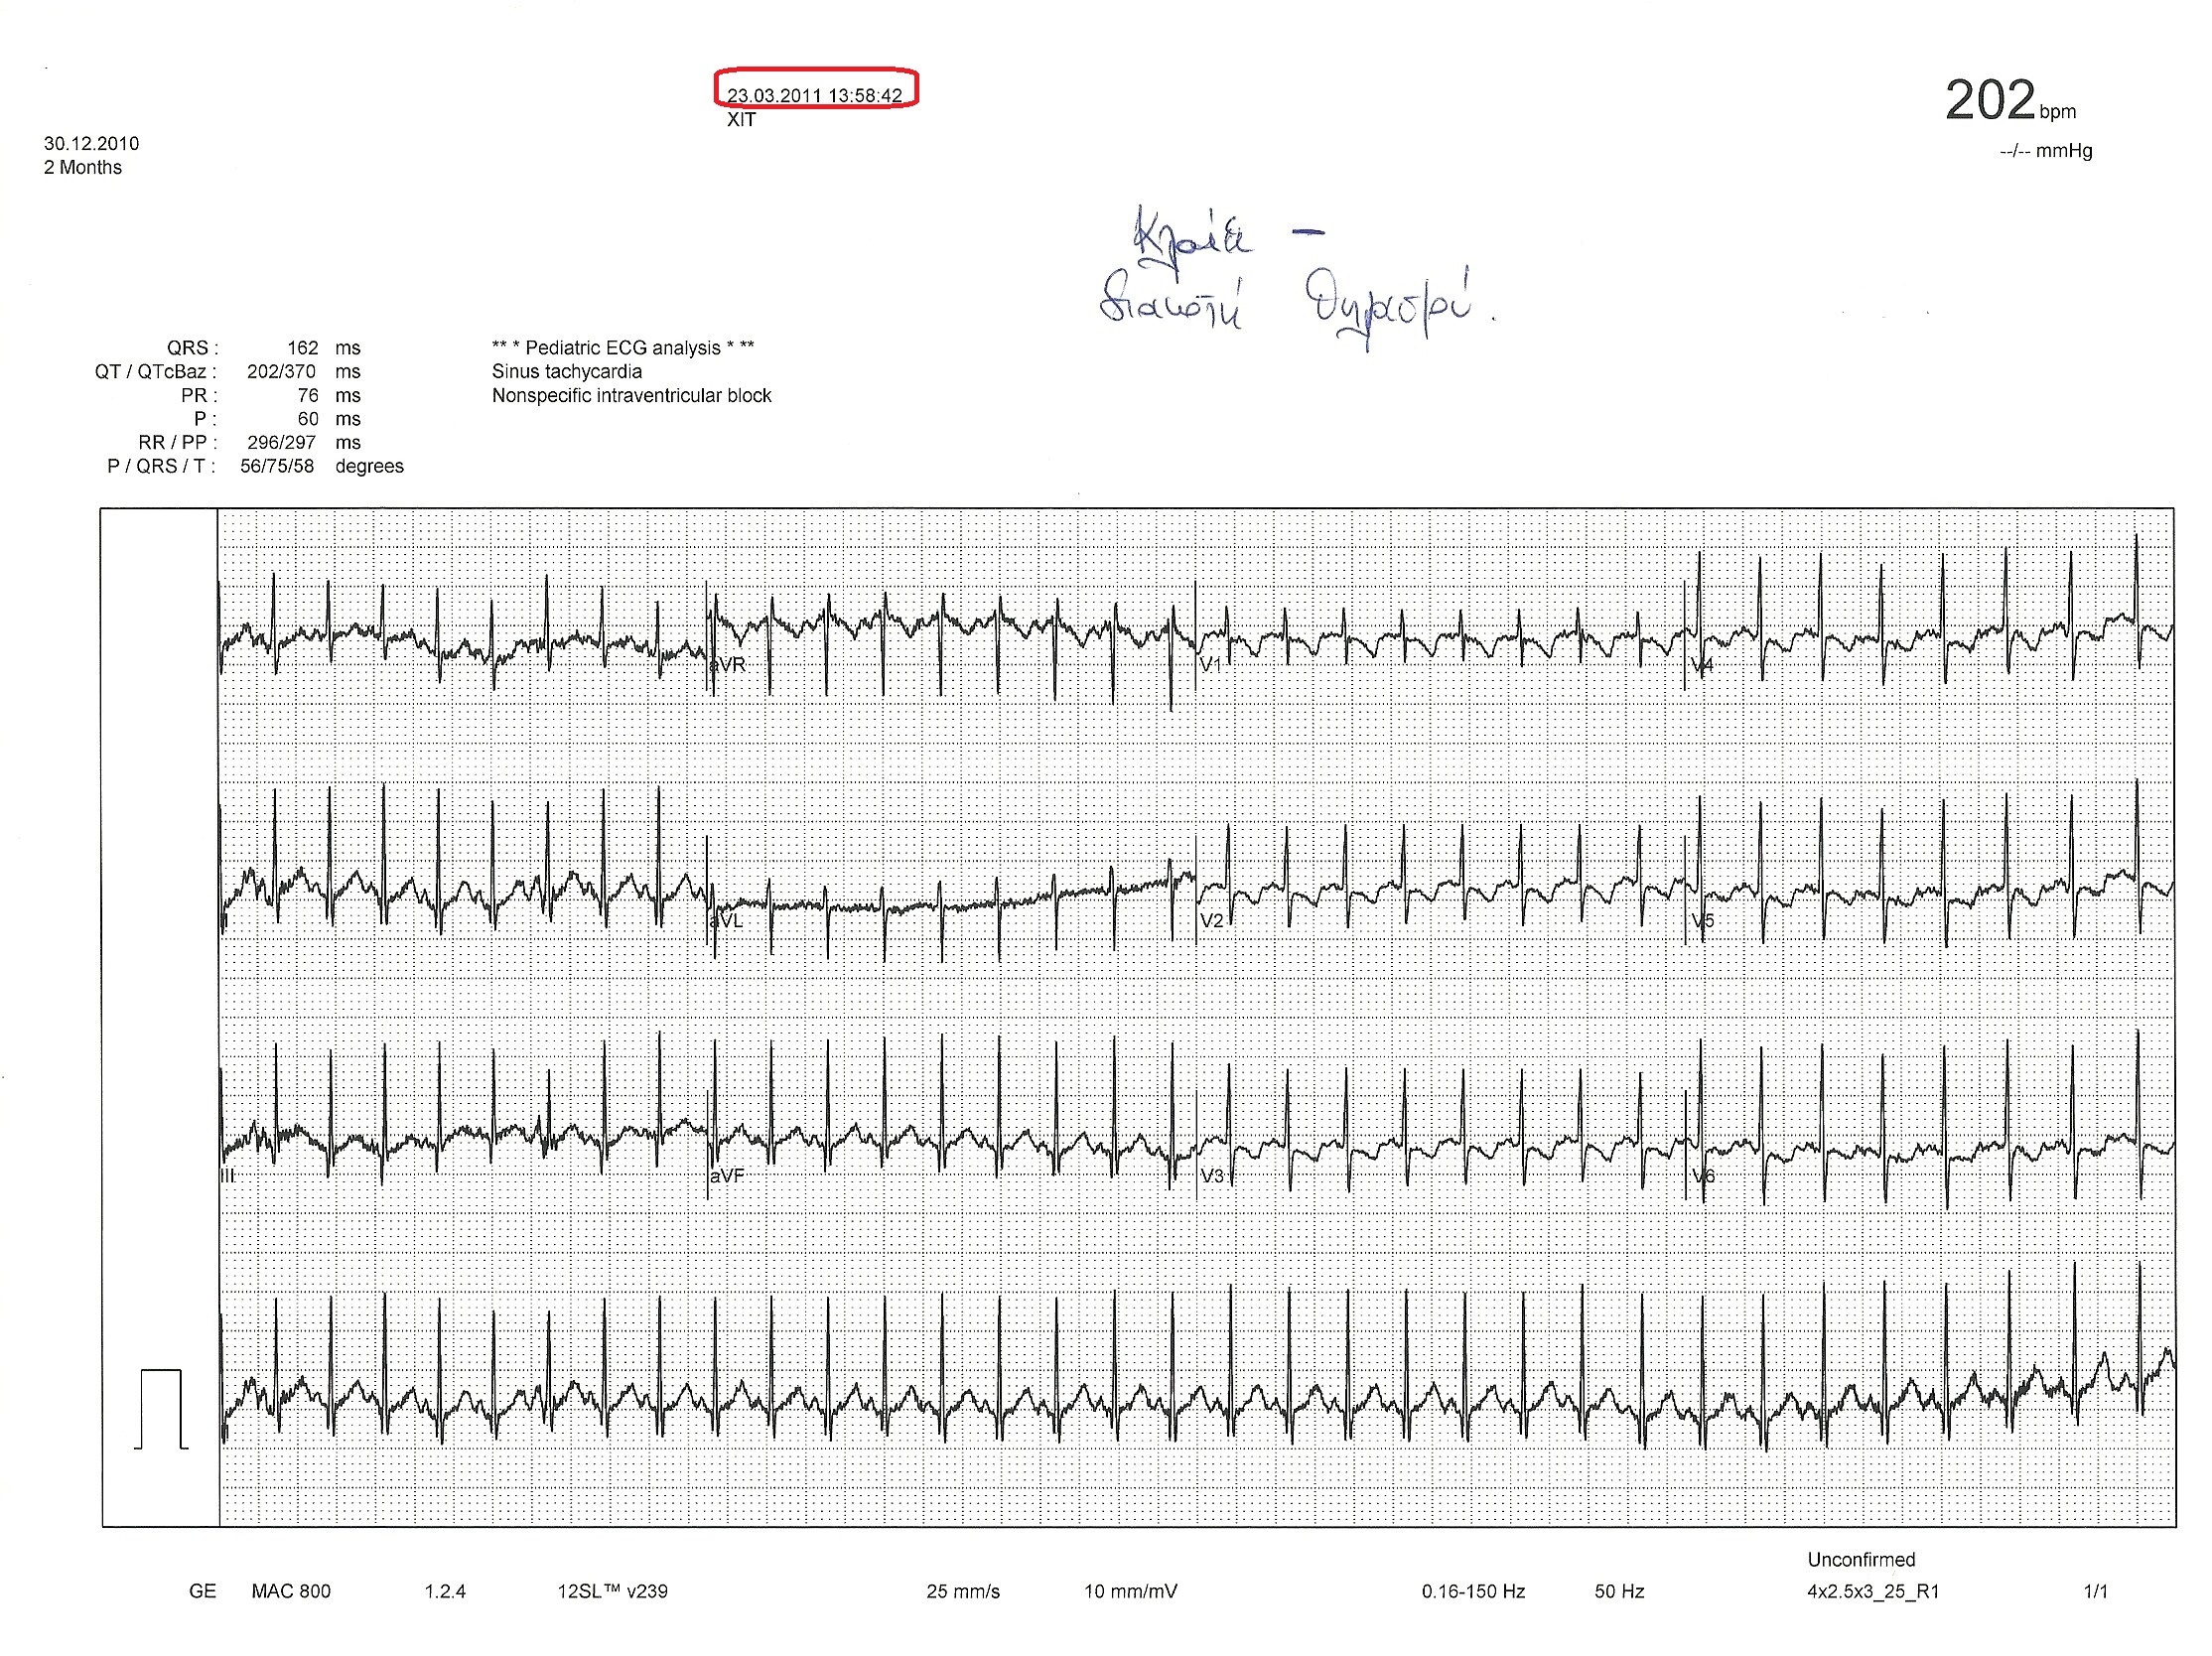

3. ΗΚΓ λίγα λεπτά μετά: έχει αρχίσει, να δυσφορεί, ενώ αρχικά είχε ηρεμήσει από το κλάμα, η επαναπόλωση διαφοροποιείται, η συχνότητα μικρότερη της προηγούμενης (163c/min).

Σημείωση: τα ΗΚΓ παρουσιάζονται με την σειρά λήψης (βλέπε ημερομηνία και χρόνο στις καταγραφές). Για προφανείς λόγους έχει απαληφθεί το όνομα του παιδιού.